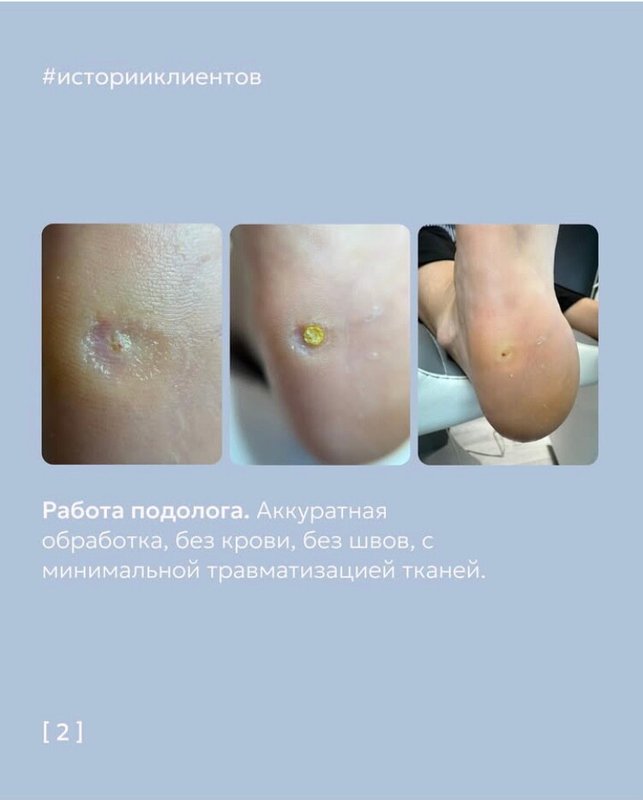

Я обратилась для удаления старой глубокой мозоли и добилась нужного результата, всё прошло и исчезло. Мне было важно избавиться от этой проблемы, специалист выполнил работу профессионально. Мне также дали необходимые рекомендации после удаления.

Услугу выполнили на удивление оперативно, и я остался доволен. Врач детально рассказал, как будет проходить удаление бородавки, после чего дал понятные советы по уходу. Теперь ранка заживает без проблем и постепенно подсушивается.

Визит в центр для удаления бородавки на стопе прошёл просто отлично! Меня поразил высокий профессионализм доктора Ольги Игоревны. Всё было сделано настолько качественно, что мне понравился каждый аспект приёма.

Я получила желаемый результат - моя проблема была полностью устранена, бородавку обработали тщательно и качественно. Ольга Игоревна оказалась настоящим специалистом, ее доброжелательное отношение ко мне вдохновило довериться ей снова. Центр я выбрала по совету, поскольку слышала, что врач успешно помогала в сложных случаях, с которыми другие не справились.